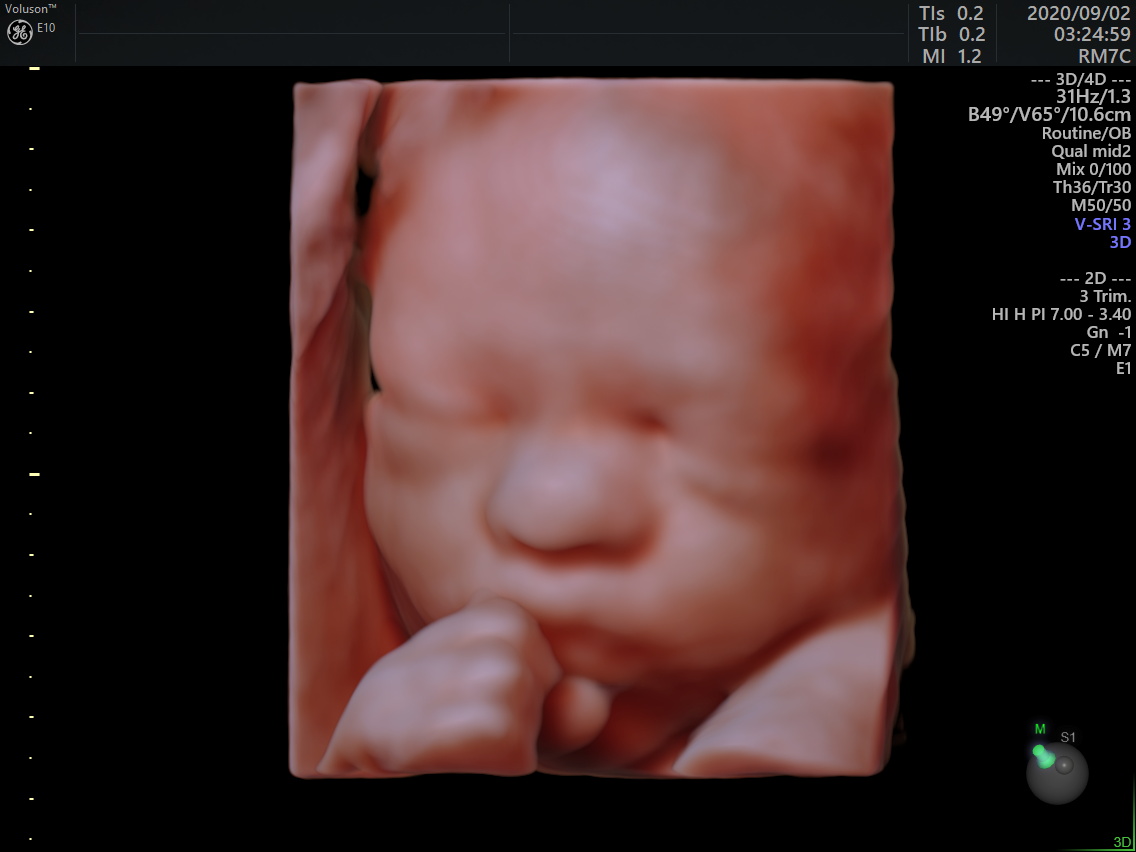

- 2025年5月より4Dエコーの料金の変更になります

-

平素より新宿南口レディースクリニックをご利用いただき、誠にありがとうございます。

当クリニックでは、より高品質な画像提供と快適な診療環境の維持に努めております。

このたび、4Dエコーに関する機器メンテナンス費用や運用コストの上昇に伴い、誠に勝手ながら2025年5月より4Dエコーの料金を7700円(税込)から8800円(税込)に改定させていただくこととなりました。

ご負担をおかけすることになり大変心苦しい限りではございますが、今後も安心・安全な診療と、より良いサービスの提供を目指してまいりますので、何卒ご理解とご協力のほどよろしくお願い申し上げます。